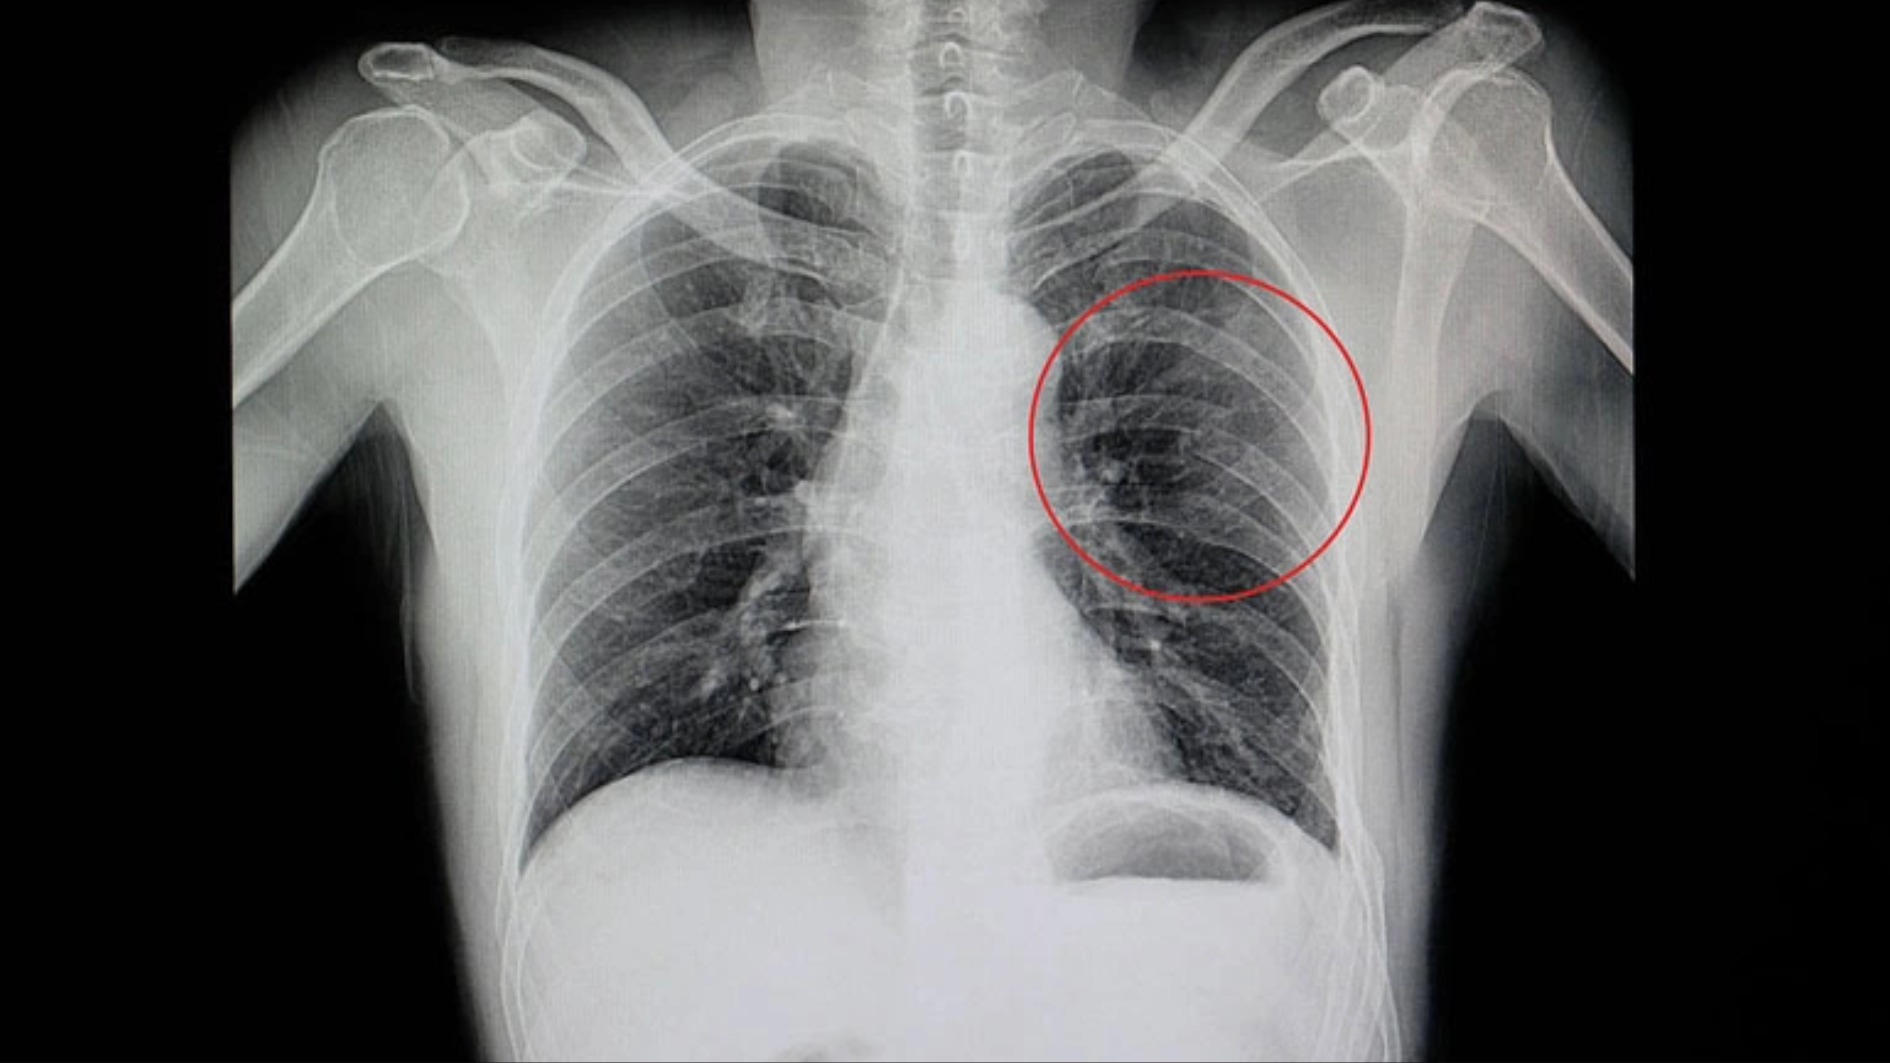

Thông thường, xương sườn gãy có khả năng tự lành mà không cần phẫu thuật. Trong giai đoạn đầu, cơ thể hình thành mô sụn tại vị trí gãy, sau đó chuyển dần thành mô xương vững chắc. Quá trình này thường kéo dài vài tháng, và phải khoảng 6 tháng thì phim X-quang mới thấy xương hoàn toàn lành.

Trong thời gian xương lành, điều quan trọng là giảm đau tốt trong tháng đầu, hạn chế vận động mạnh hoặc chấn thương thêm. Việc chụp X-quang kiểm tra không cần thiết nếu cơn đau giảm dần; chỉ nên tái khám hoặc chụp lại phim nếu xuất hiện đau tăng, khó thở, mệt mỏi, hoặc các dấu hiệu bất thường khác.

Đâm thủng phổi

Phổi nằm ngay dưới khung xương sườn, nên khi xương sườn gãy, các mấu nhọn của xương có thể làm phổi bị rách hoặc trầy xước, gây đau và thậm chí thủng phổi, một tình trạng vô cùng nguy hiểm.